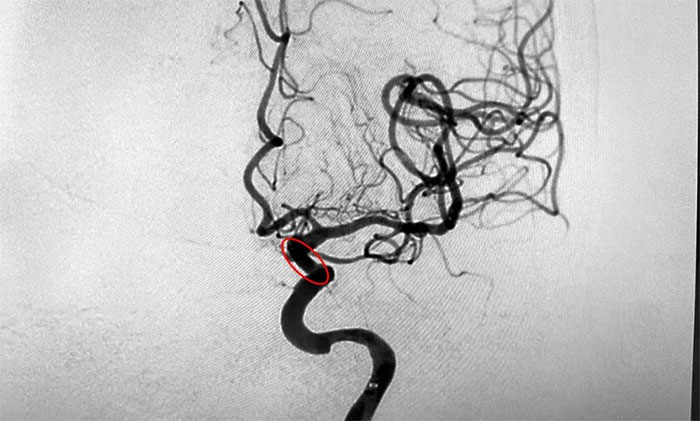

臨床上,狹窄高于50%低于70%有明顯癥狀,或狹窄高于70%,以及檢查發(fā)現為不穩(wěn)定斑塊者,應通過手術治療予以干預。在明確指征,排查手術禁忌,進一步完善手術預案并獲得家屬同意后,席剛明教授為患者進行了左頸內動脈球囊擴張+支架置入手術。術中,隨著支架的順利置入,造影可見左頸內動脈眼動脈段狹窄明顯得到改善。

▲ 術后可見狹窄明顯改善